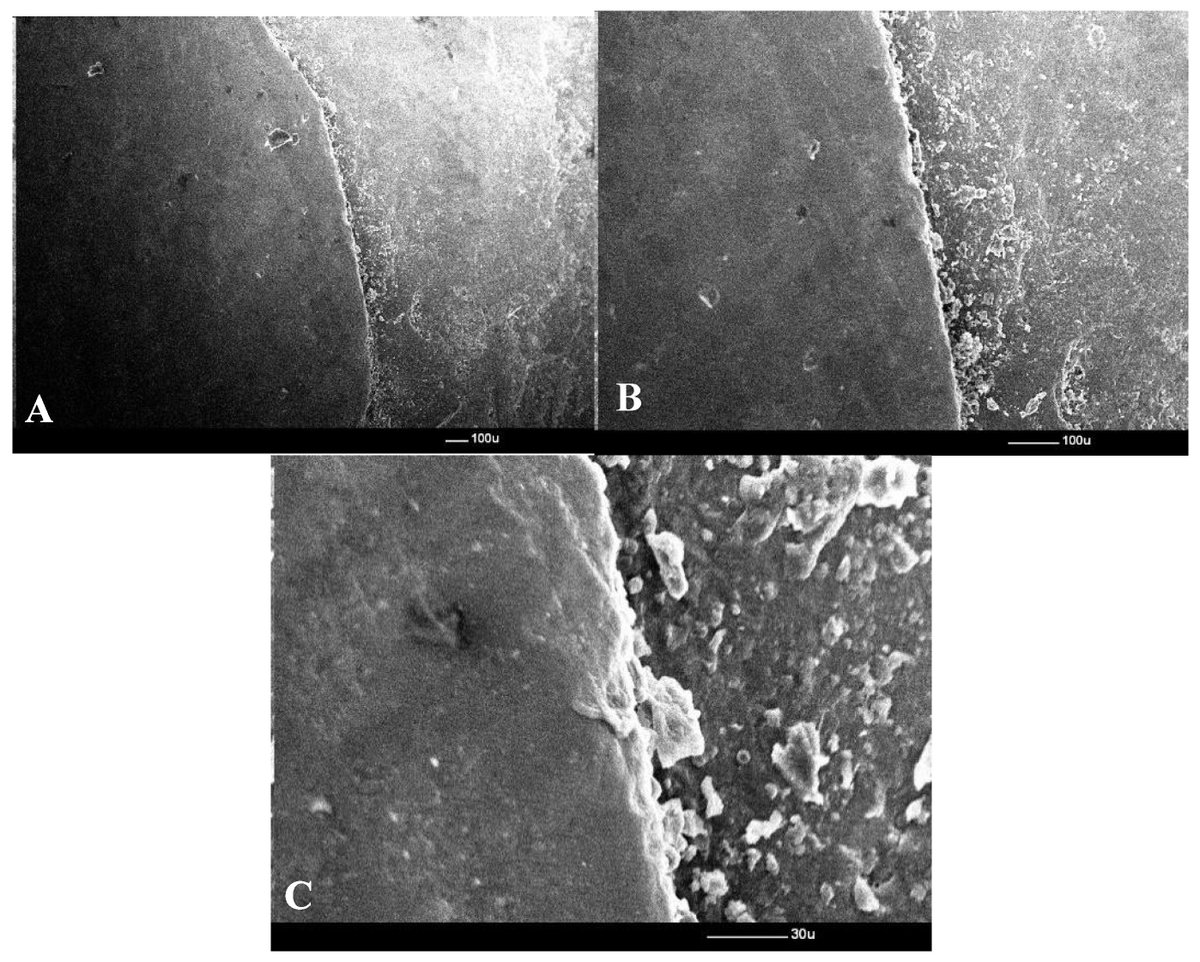

In vitro SEM study: Cerasmart & G-CAM (hybrid/resin nanoceramics) have narrower marginal gaps than IPS Empress CAD 🦷🔬. All meet clinical thresholds, enhancing single-unit crown durability! https://t.co/32ILwxp3k2 #CADCAMRestorations #DentalProsthetics #MarginalAdaptation